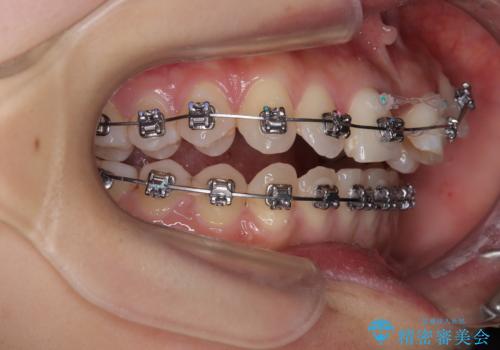

- 矯正装置

- メタルブラケット

- 治療期間

- 1年8ヶ月

- 治療回数

- 30回以上